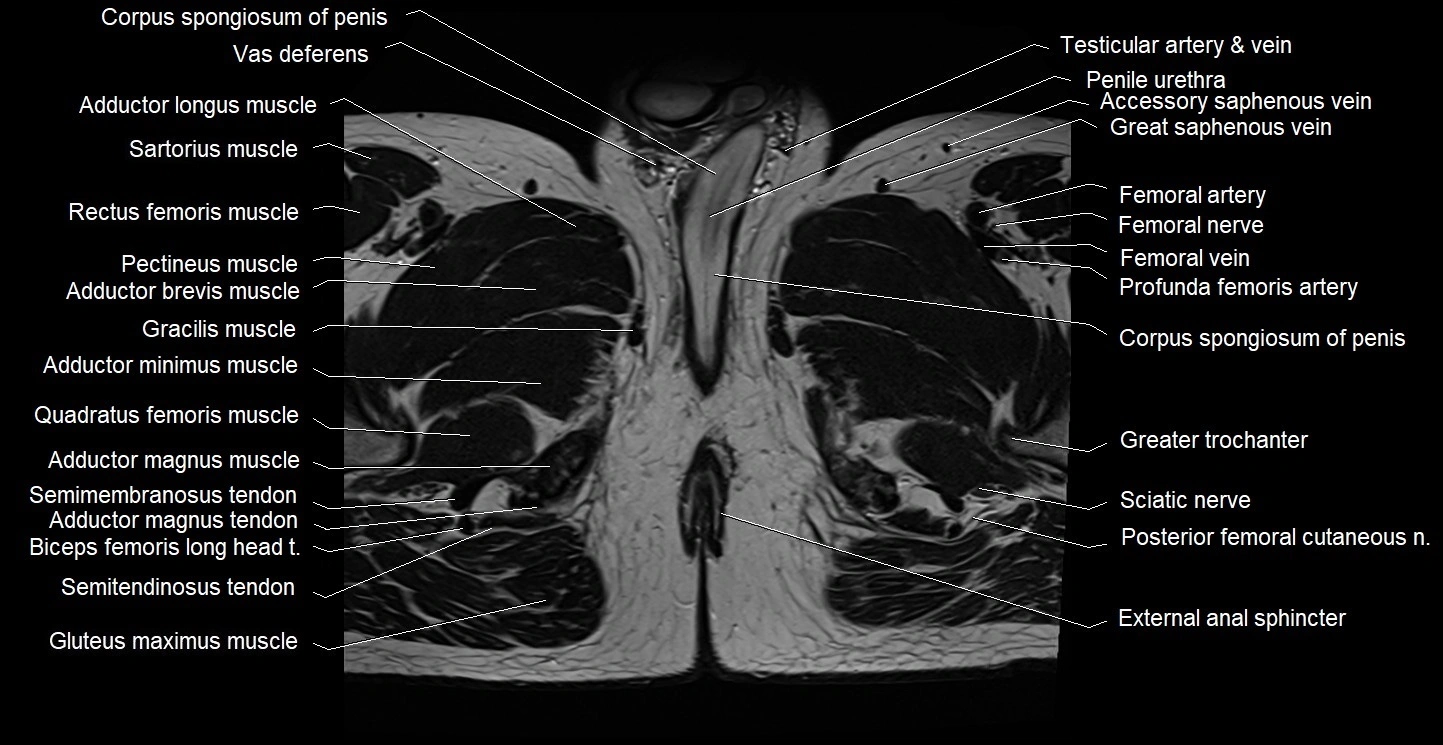

- External anal sphincter

- Femoral nerve

- Femoral shaft

- Femoral vein

- Gluteus maximus muscle

- Gracilis muscle

- Greater trochanter

- Posterior femoral cutaneous nerve

- Sciatic nerve